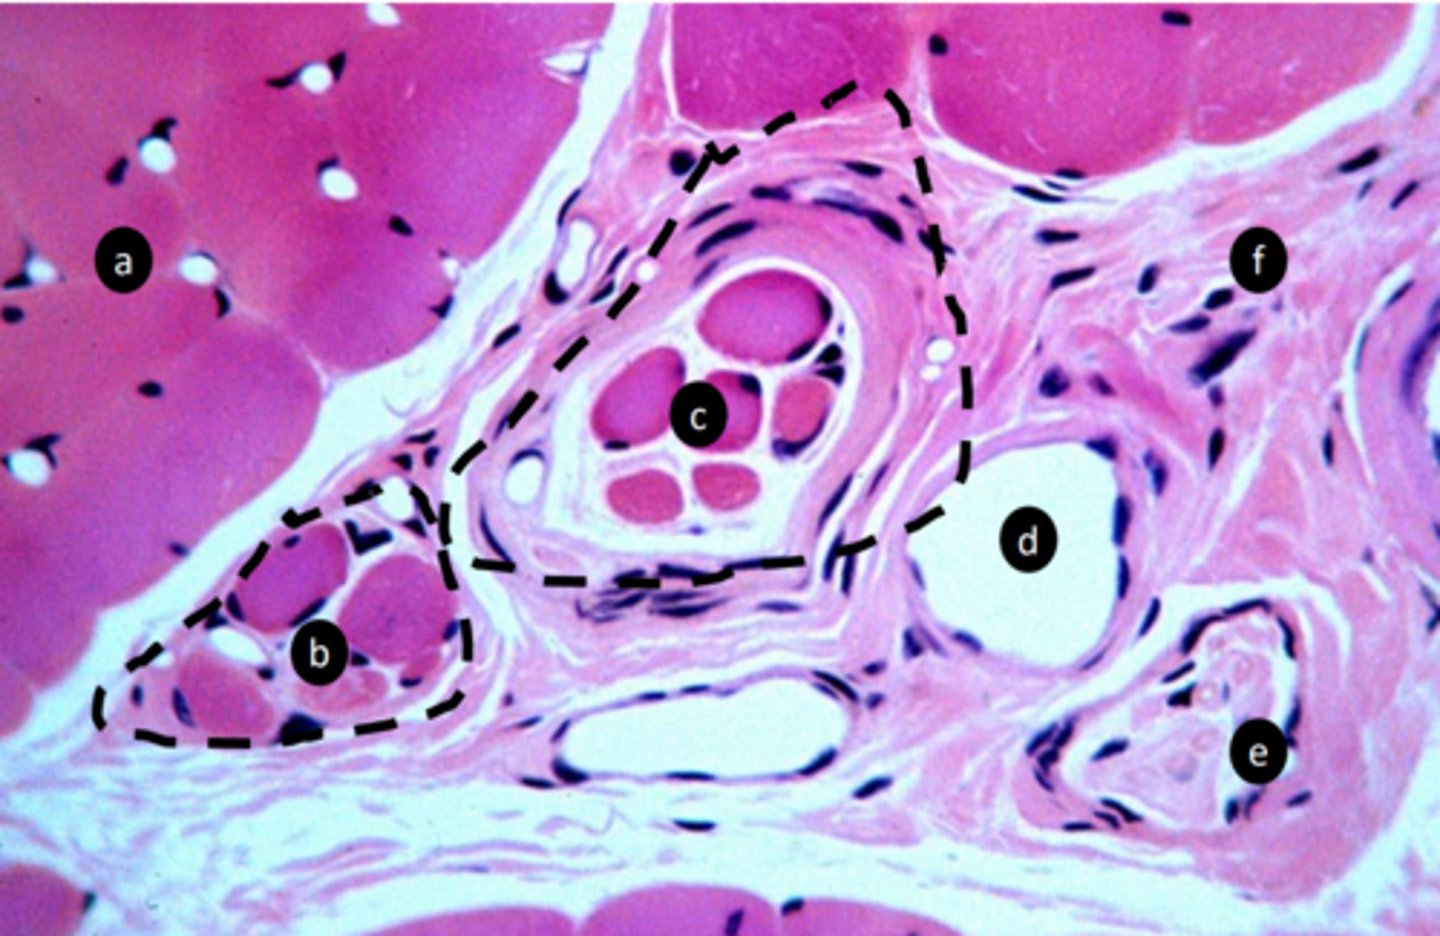

a: specific tissue type

extrafusal myofibers

b: specific tissue type

intrafusal muscle fiber

c: specific tissue type

intrafusal muscle fiber (muscle spindle)

function of c?

stretch receptor, proprioception: detect length and velocity

e: structure

vein

f: structure

nerve fibers

g: tissue type

CT